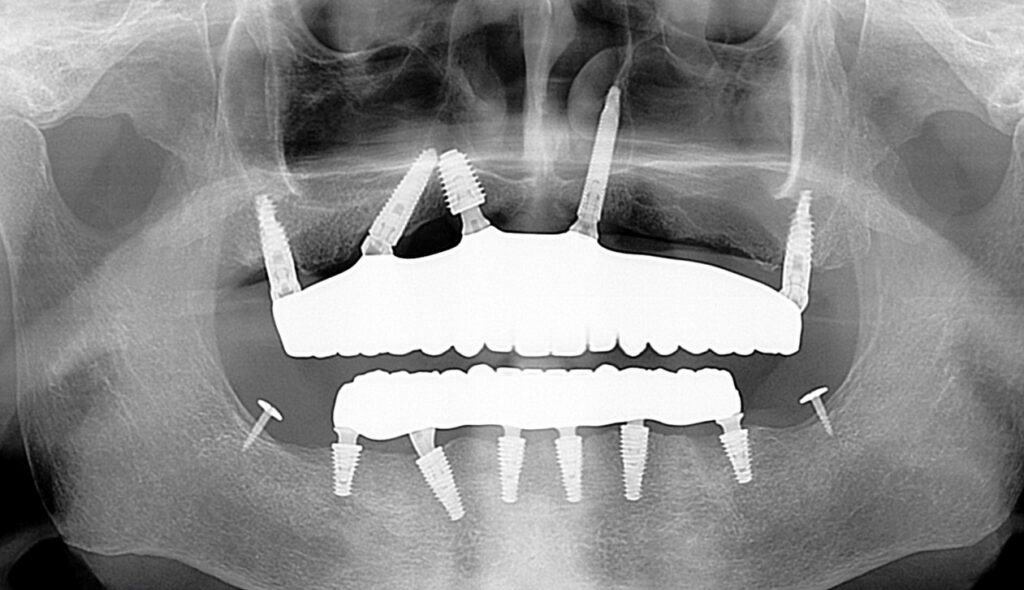

This course offers advanced training in implant solutions for the atrophic maxilla using the PATZi Protocol. Participants will learn how to confidently implement zygomatic, pterygoid, trans-sinus, and nasalis implant techniques while integrating a fully digital workflow for precise surgical planning and prosthetic delivery.

- Understand the clinical indication, anatomical considerations, and surgical protocols for zygomatic, pterygoid, trans-sinus and nasalis implants.

- Gain proficiency in the PATZi Protocol as a comprehensive solution for treating atrophic maxilla cases.

PATZi Protocol, Zygomatic, Pterygoid, Trans-Sinus, Nasalis Implant Protocols with Full Digital Workflow